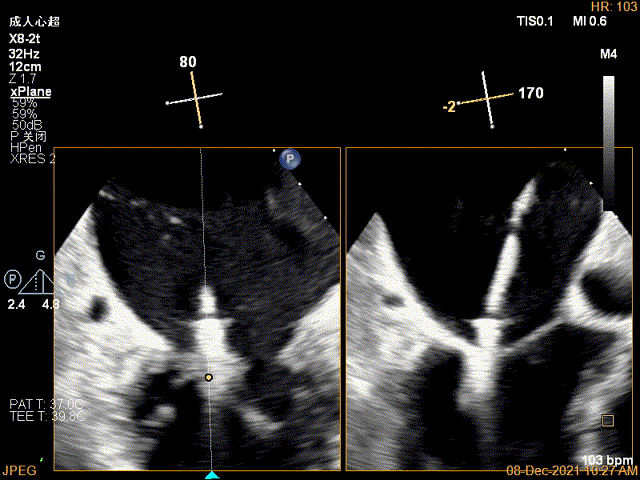

X-plane:下夹子尝试先捕获2区瓣叶

夹子关闭过程中,Color提示2区反流逐渐减少,残余反流位于夹子外侧